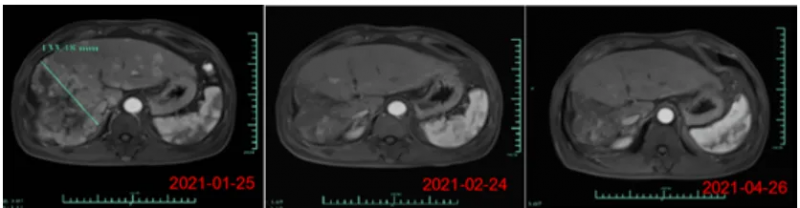

《肿瘤靶点和治疗》杂志曾报道一则极具参考价值的临床案例:一名59岁男性患者,因慢性乙肝病史,不幸确诊IV期弥漫性肝细胞癌(HCC)。此前,他虽接受了经导管动脉化疗栓塞术(TACE)、腹膜穿刺手术及顺铂等多种治疗,但病情仍持续恶化。随后,患者入组接受NK细胞治疗。

结果显示:在完成6个疗程治疗后,CT复查提示腹水几乎完全消退,胸腔积液也彻底消失。更令人振奋的是,当完成全部17个疗程治疗后,CT影像进一步证实,其右肝叶多处肿瘤病灶显著缩小(详见下图)。这一案例为NK细胞治疗晚期肝癌的有效性提供了有力佐证。

▲图源“Dovepress”,版权归原作者所有,如无意中侵犯了知识产权,请联系我们删除